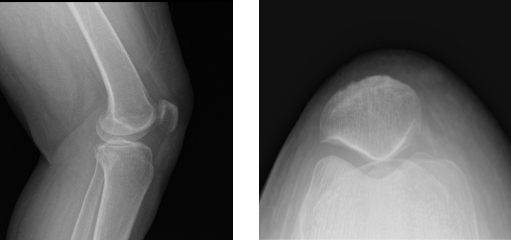

X-ray results presented and reviewed showed that there are no degenerative diseases. Advised patient to undergo MRI and found out that there is subcutaneous edema anteriorly and anteromedially.

Suspected tear in the posterior horn of the medial meniscus. There is a very faint oblique signal that appears to extend to the inferior articular surface. There is partial tear of the proximal PCL and mild chondromalacia patella and deep infrapatellar bursitis were also observed.

Left Knee X-ray Complete with patella